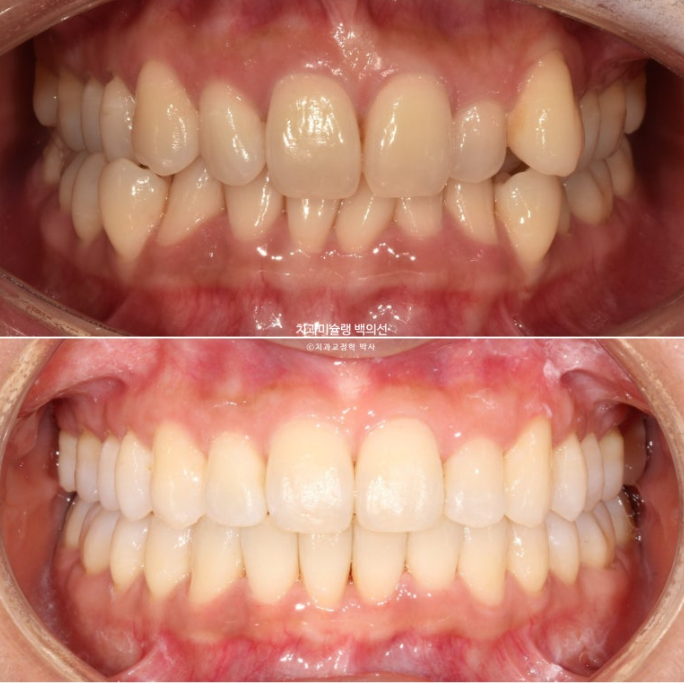

옥니, 덧니, 과개교합, 반대교합, 중심선 불일치 등 다소 복잡해 보이지만 환자분이 잘 껴주어 예상보다 치료가 빠르게 마무리된 케이스를 보겠습니다.

24.08~25.08

치료기간을 1년 반 예상했지만 환자분이 장치를 잘 껴준 덕에 1년만에 마무리가 되었습니다.

전후 보겠습니다.

중심선, 과개교합, 덧니의 개선